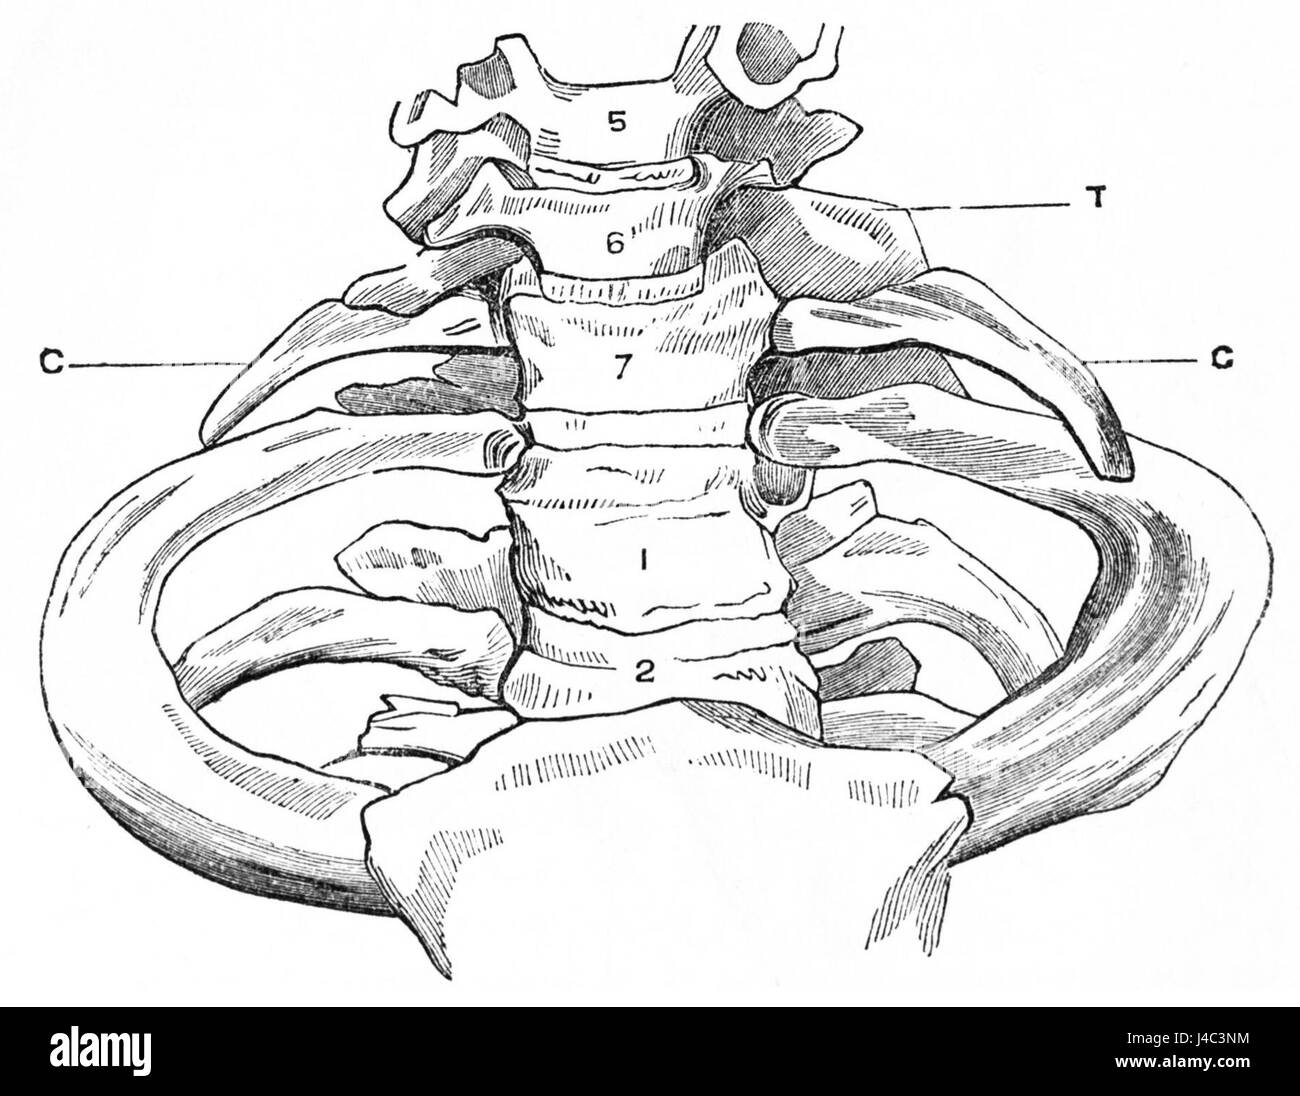

RMJ4C3NM–Questo diagramma di PSM V25 D742 illustra la struttura anatomica delle costole cervicali e il processo trasversale delle vertebre cervicali. È una rappresentazione dettagliata utilizzata nello studio dell'anatomia umana, concentrandosi sulla struttura vertebrale e sullo sviluppo delle costole.